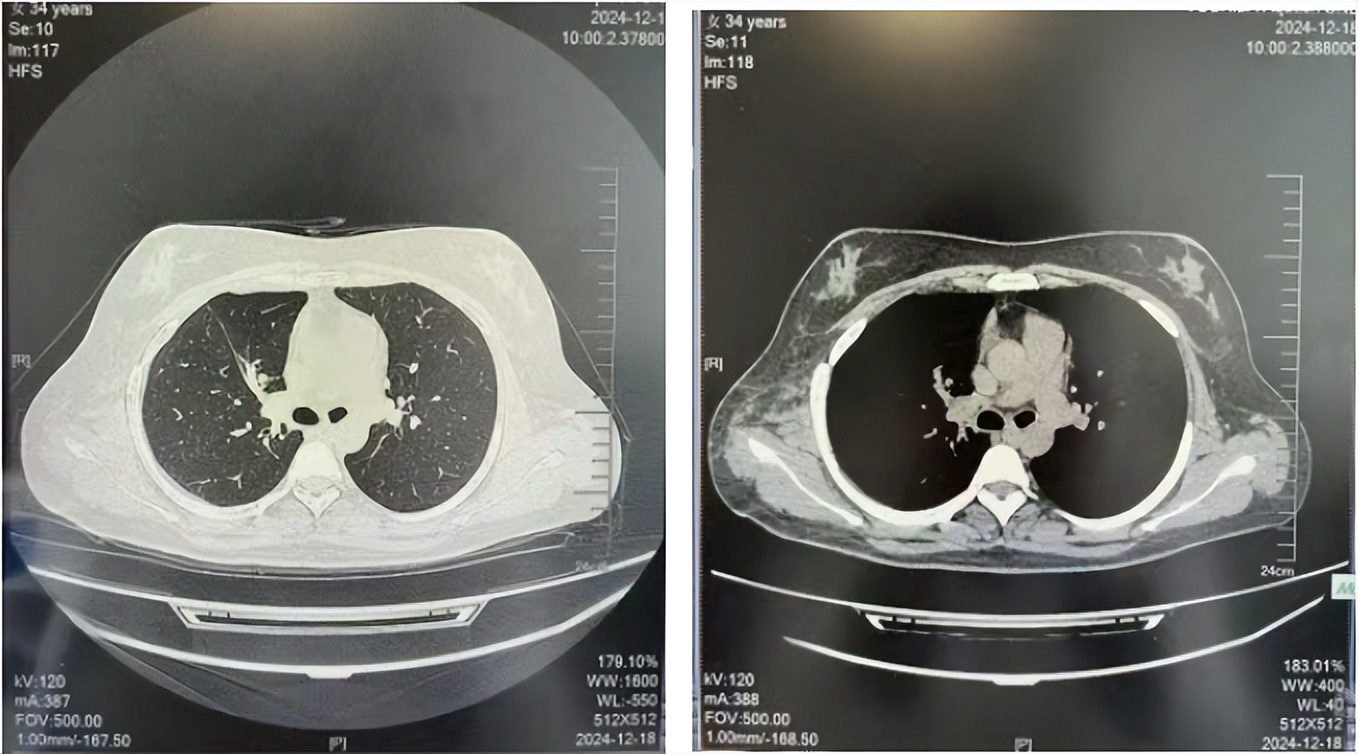

2024.12

治疗经过:2023年3月27日始行恩沙替尼靶向治疗至今,最佳疗效为PR,末次评效为维持PR。期间出现轻度肝功能异常(DILI 1级),对症处理后好转。截止目前PFS为26个月。

2024年12月复查维持PR

2025年3月复查维持PR